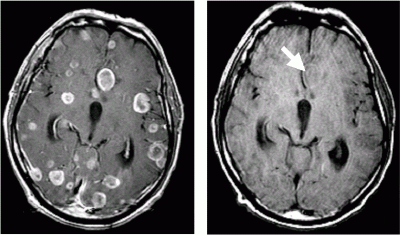

Помимо принятых обследований во время МРТ, КТ, УЗИ, рентгена проводится визуальное обследование глазного дна, состояние кровеносных сосудов проходящих по этому органу. При каких-либо появившихся нарушениях, отмечается потеря остроты зрения, слуха.

КТ головного мозга

- Компьютерная томография может визуализировать даже бессимптомные поражения у больных с экстракраниальными повреждениями (которые находятся на поверхности органа).

- МРТ ‒ золотой стандарт диагностики прогрессивных раковых опухолей в этих областях. В зависимости от вида вторжения, изменяется качество изображения.